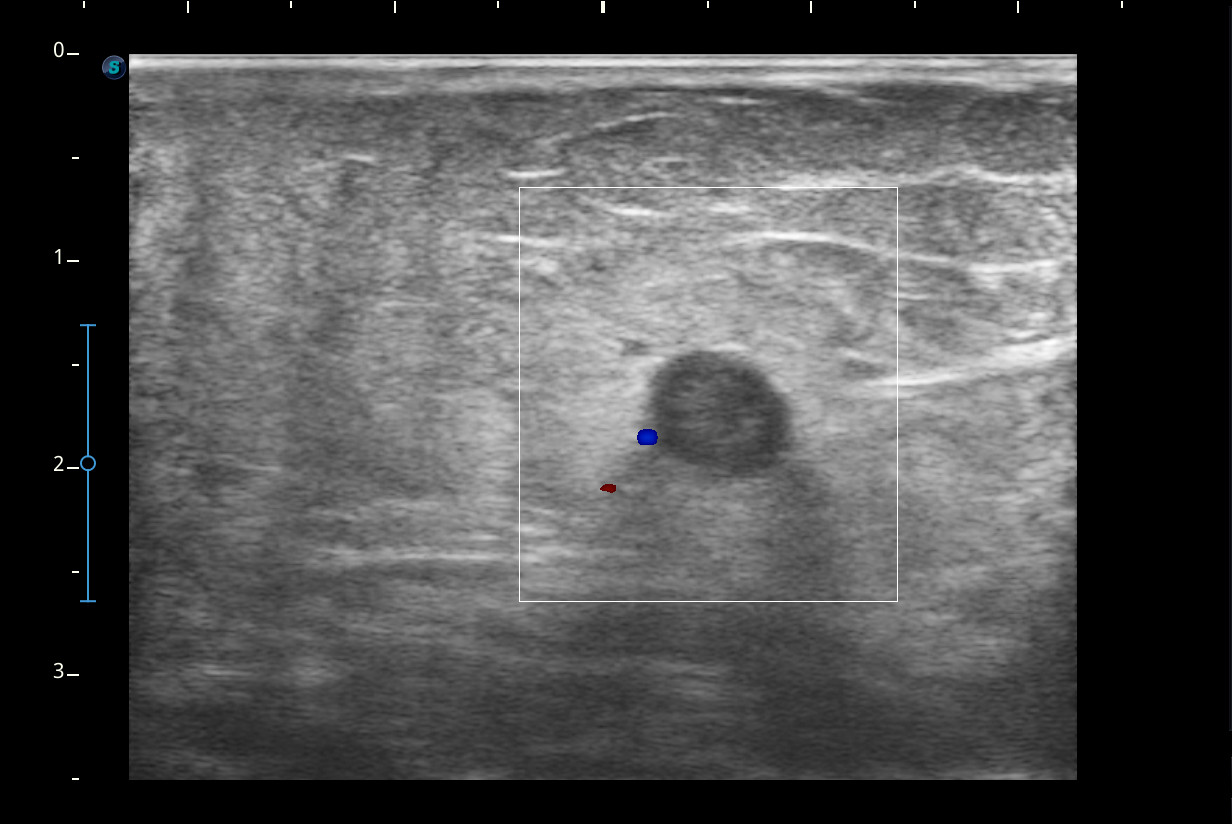

Hallazgos ecográficos

Se visualiza congestión del tejido subcutáneo del brazo y ocupación de la luz de la vena basílica del brazo por un trombo.